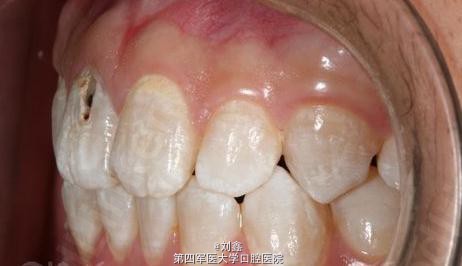

患者男 23岁,学生,目标是做一名主持人,但是因从小家乡水质不好,所以形成了氟斑牙,要求铸瓷贴面修复。

11有深龋,氟斑牙

患者下牙的牙龈较薄,但是因制备中的疏忽仍然选用了00的排龈线,使下牙牙龈在排龈中受到损伤,在戴牙后发现32的牙龈萎缩1MM,形成了“龈上肩台”。